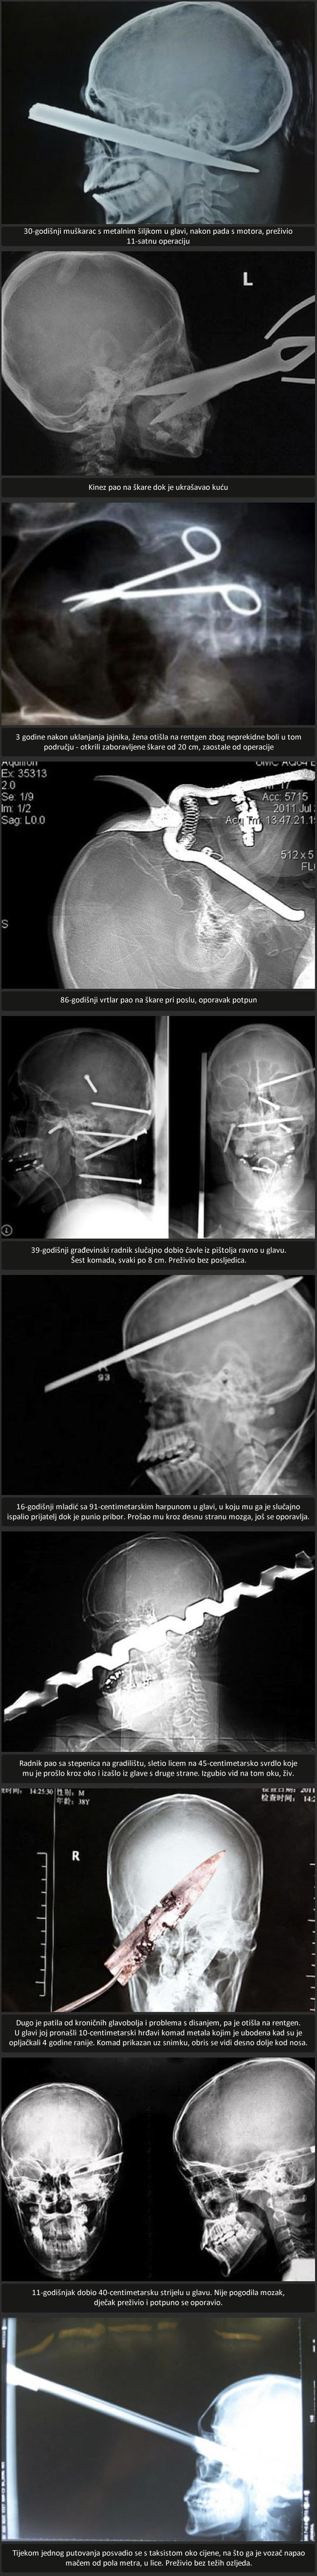

Najstravičnije rentgenske snimke nesreća

Mač u glavu, harpun, škare.. ljudi su otporniji nego mislimo :O